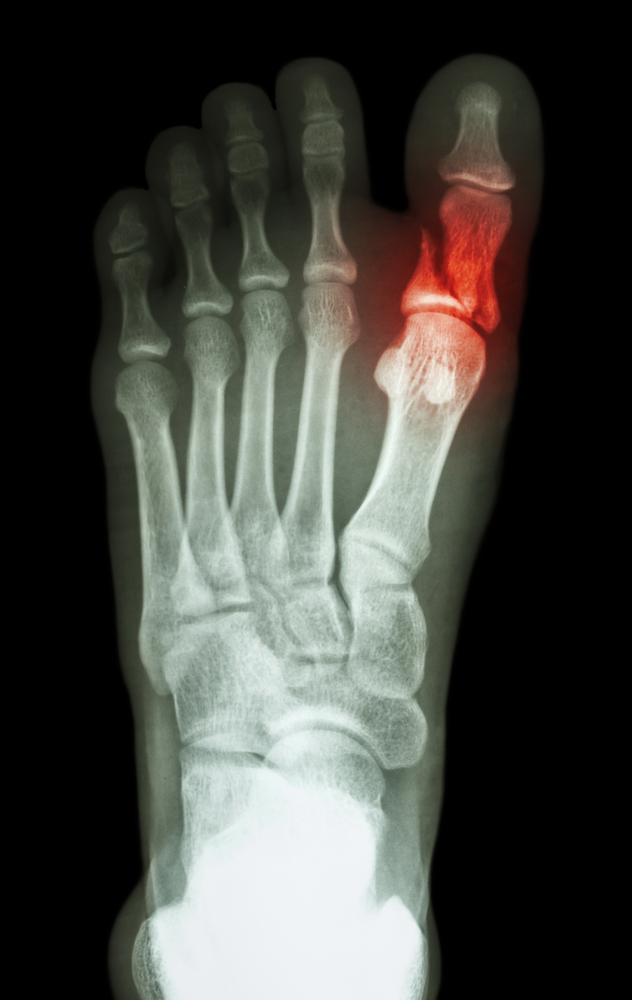

발가락 골절은 흔히 발생하는 상황입니다. 이유는 다양하게 있을 수 있으며, 대표적으로는 실내에서 물건에 부딪히거나 높은 곳에서 떨어지는 등의 사고가 있습니다. 이 외에도 스포츠 활동 중 부상을 당하거나 교통사고 등에서도 발가락 골절이 발생할 수 있습니다. 발가락 골절은 크게 뼈가 완전히 부러진 경우와 뼈에 금만 간 경우로 나눌 수 있으며, 이에 따라 치료 방법과 기간이 다릅니다.

- 깁스 치료: 뼈가 크게 부러진 경우에는 깁스로 고정하는 방법이 일반적입니다.

- 스플린트: 뼈에 금만 간 경우, 즉 미세한 골절의 경우에는 발가락용 스플린트로 치료가 가능합니다.